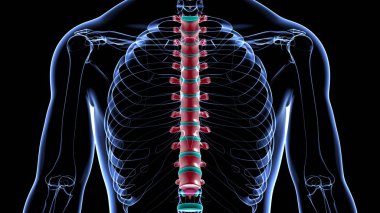

İnsan iskeleti anatomisi Scapula Kemiği Tıbbi Konsept için 3D Hazırlama

İskeletanatomiçene kemiğiyarım ayboyunlomberetmoidcapitateAltkısmınıHamate3d oluşturmaGöğüs kafesi3B illüstrasyoncarpalsağız sapımetakarplaralın kemiğiApendiküleruyluk kemiğioksipital kemikBurun kemiğikemiğigöğüs kemiğinin gövdesiayak kemikleriyarıçap kemiğiparietal kemikeksenel iskeletKalça kemiğilacrimal bonepalatine boneproximal phalangesinferior nasal conchaintermediate phalangesdistal phalangesclavicle bonekaval kemiğiBurun kıkırdağıkol kemiğikürek kemiğiBenzer İçerikler